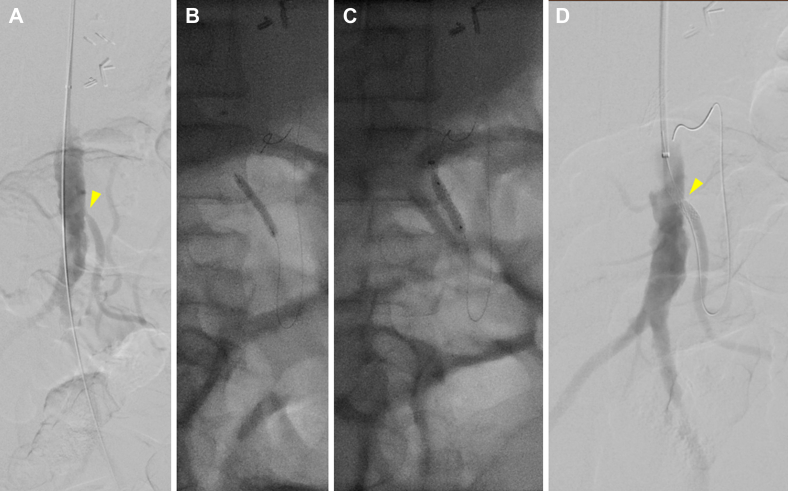

Fig 1.

A, Preoperative flush aortogram of patient 1 demonstrating severe inferior mesenteric artery (IMA) stenosis (arrowhead) with steep angulation accommodated by a brachial approach. The aortoceliac bypass is not visible. B, Balloon angioplasty. C, Subsequent stent placement. D, Completion angiogram showing improved IMA stenosis (arrowhead).

Patient 1

A 47-year-old female patient with multiple prior lower extremity bypasses and chronic mesenteric ischemia, with stenting of the SMA 1 year earlier, had presented to an outside institution with severe sudden-onset abdominal pain. Computed tomography (CT) demonstrated small bowel pneumatosis with portal venous gas, and the patient underwent urgent exploration, including ileocecectomy with primary ileocolic anastomosis. Postoperatively, the patient’s diet was advanced; however, on postoperative day (POD) 12, abdominal pain and distention had developed. CT angiography (CTA) demonstrated celiac artery and SMA occlusion with IMA stenosis. The patient was transferred to our institution, and heparin was administered for anticoagulation. The patient was then taken to the operating room for aortoceliac bypass. However, the graft had repeatedly thrombosed intraoperatively. Thus, empirically, the heparin was transitioned to argatroban, facilitating closure with a patent bypass. The patient was not able to tolerate an oral (per os [PO]) diet postoperatively. A CT scan demonstrated patency of the bypass but persistent stigmata of mesenteric ischemia. The patient underwent mesenteric angiography via a left brachial approach on POD 10 of 22, demonstrating a patent bypass with high-grade ostial IMA stenosis. Despite the patent celiac graft, the viscera remained poorly perfused. The IMA was stented with a bare metal stent after initial percutaneous transluminal angioplasty had resulted in a focal dissection and significant elastic recoil, with significant improvement seen on completion angiography (Fig 1). Postoperatively, the patient improved, the diet was advanced without consequences, and the remainder of the hospital course was unremarkable. The patient was discharged with warfarin anticoagulation therapy and was noted to have a patent bypass and IMA on duplex ultrasound 1 year postoperatively, after which point the patient was lost to follow-up.